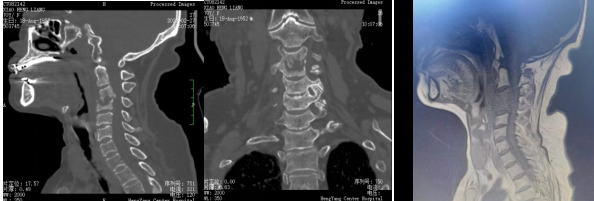

患者入院后完善相關(guān)檢查,不查不知道,一查不簡(jiǎn)單:患者頸椎疼痛不是簡(jiǎn)單的肌肉勞損,而是頸椎骨頭出現(xiàn)了破壞、塌陷,神經(jīng)受壓。由于患者頸椎病變位置較高,骨質(zhì)破壞范圍較大,并后凸、脊髓受壓,椎體穩(wěn)定性差,稍有不慎容易出現(xiàn)災(zāi)難性后果?,F(xiàn)有的重建材料難以達(dá)到好的臨床效果,蘇光輝主任團(tuán)隊(duì)采用先進(jìn)的3D打印技術(shù),為患者進(jìn)行了個(gè)性化手術(shù)方案及假體設(shè)計(jì),假體與需要切除骨質(zhì)完美匹配,最大程度恢復(fù)解剖結(jié)構(gòu)及重建的穩(wěn)定性,對(duì)假體進(jìn)行骨小梁結(jié)構(gòu)設(shè)計(jì),具有良好的骨長(zhǎng)入效果,能夠減少假體下沉及松脫等術(shù)后并發(fā)癥的發(fā)生。

術(shù)前影像:C3、4椎體病變,椎管狹窄